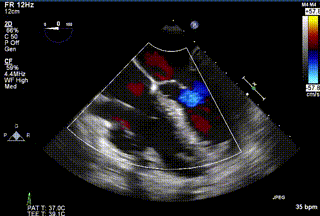

患者三术前心超

患者三术后心超